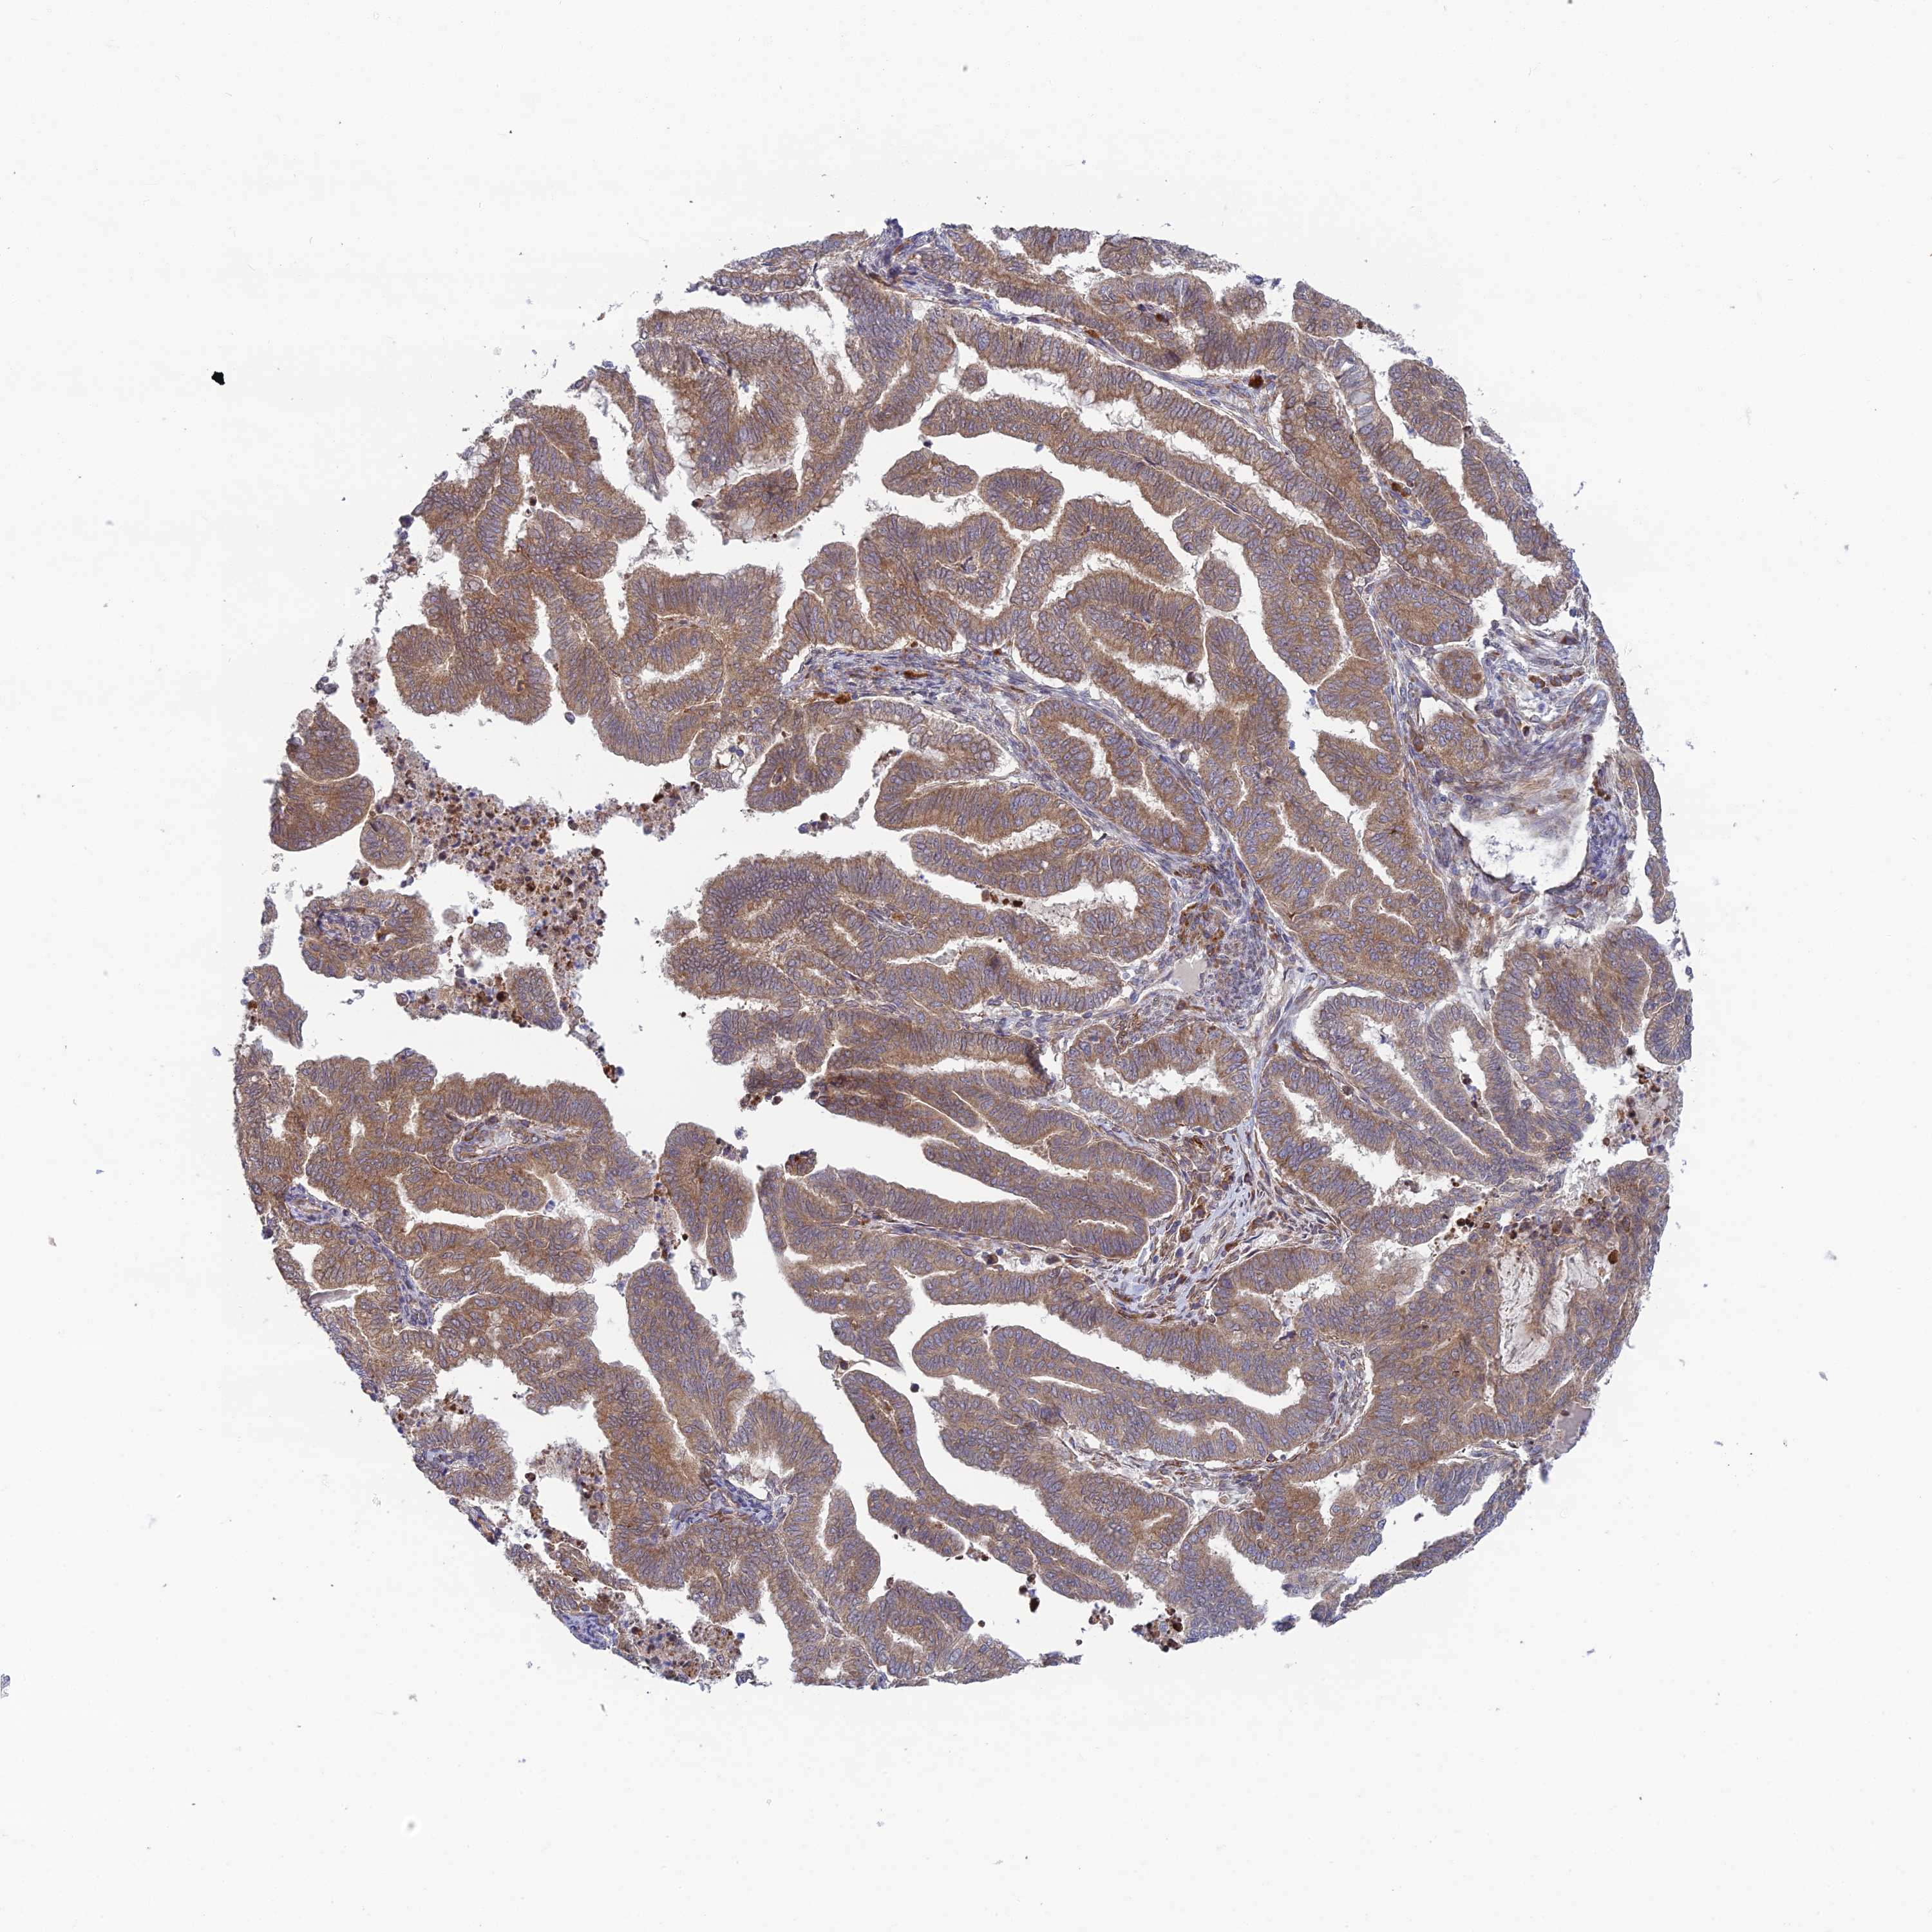

ENDOMETRIAL CANCER - Protein expressioni

A mouse-over function shows sample information and annotation data. Click on an image to view it in a full screen mode. Samples can be filtered based on level of antibody staining by selecting one or several of the following categories: high, medium, low and not detected. The assay and annotation is described here.

Note that samples used for immunohistochemistry by the Human Protein Atlas do not correspond to samples in the TCGA dataset.

Antibody stainingi

Antibody staining in the annotated cell types in the current human tissue is reported as not detected, low, medium, or high, based on conventional immunohistochemistry profiling in selected tissues. This score is based on the combination of the staining intensity and fraction of stained cells.

Each image is clickable and will lead to virtual microscopy that enables deeper exploration of all samples and also displays staining intensity scores, fraction scores and subcellular localization as well as patient and tissue information for each sample.

Antibody HPA044359

Staining

High

Medium

Low

Not detected

Intensity

Strong

Moderate

Weak

Negative

Quantity

>75%

75%-25%

<25%

None

Location

Nuclear

Cytoplasmic/membranous

Cytoplasmic/membranous,nuclear

Adenocarcinoma, NOS

Adenocarcinoma, metastatic, NOS